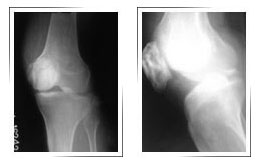

Fracture Tibial Plateau with metaphyseal extension :

Before Surgery